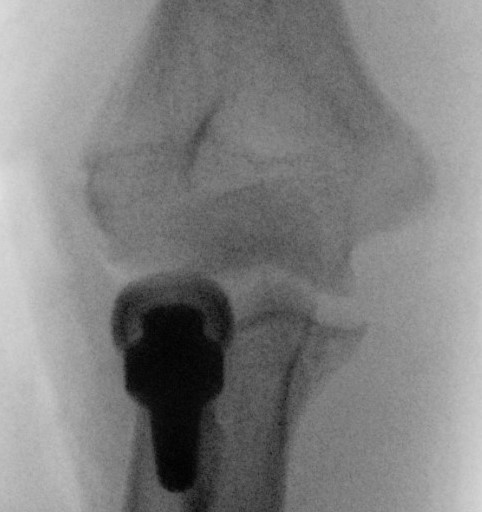

Overstuffing

| Lesser sigmoid notch | Symmetry of ulnohumeral joint |

|---|---|

|

Radial head shoulder articulate with lesser notch

Ensure no gapping of lateral ulnohumeral joint |

![]() |

- cadaveric study

- increased medial ulno-humeral joint line gapping with overlengthening of 6 or 8 mm

- increased lateral ulno-humeral joint line gapping with overlengthening of 2 mm